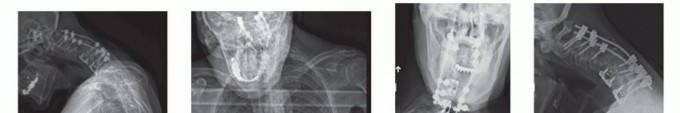

DEFINITION The precise definition of cervical kyphosis is not clearly described. Normal alignment from C2 to …